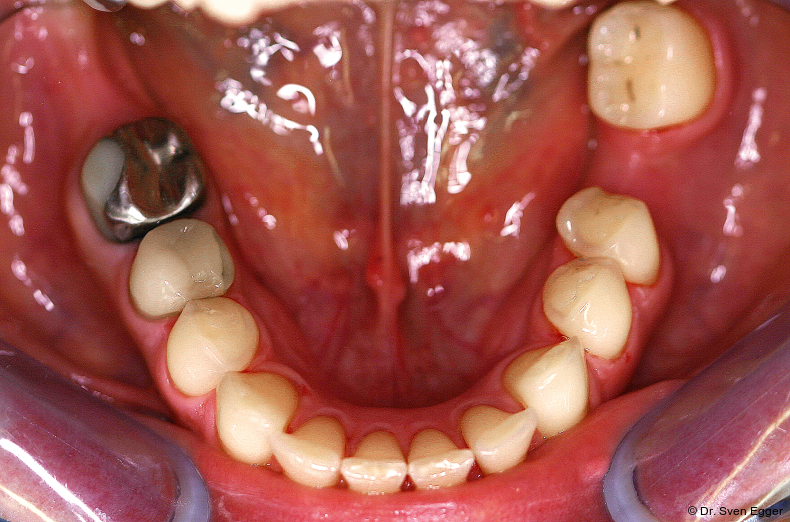

Bei der zahnmedizinischen Anamnese stellte sich ein hoher Konsum säurehaltiger Getränke (v. a. Coca-Cola light) heraus, welcher zu generalisierten Erosionen im Gebiss geführt hat. Die Zähne 36 und 47 wurden aufgrund endodontischer Vorbehandlung/Kronenfrakturen vor ca. vier Jahren entfernt. Der Leidensdruck, insbesondere verursacht durch die immer kürzer werdenden Frontzähne, bewog sie nach Aufklärung/Beratung zu einer Gesamtrestauration in allen vier Quadranten mit Presskeramikteilkronen und -veneers sowie drei Einzelzahnimplantaten.

Parodontal zeigen sich keine Auffälligkeiten. Der CMD-Kurzbefund zeigte eine Druckdolenz im Bereich M. masseter und M. temporalis. Die KG sind unauffällig.Die Zähne 17, 26 sind elongiert, 37 ist nach mesial gekippt. Es liegt ein Tiefbiss vor.

- Parafunktion mit massivem Zahnhartsubstanzverlust(Erosionen/Abrasionen) bei bestehender Deckbisssituation

- Störung der statischen und dynamischen Okklusion